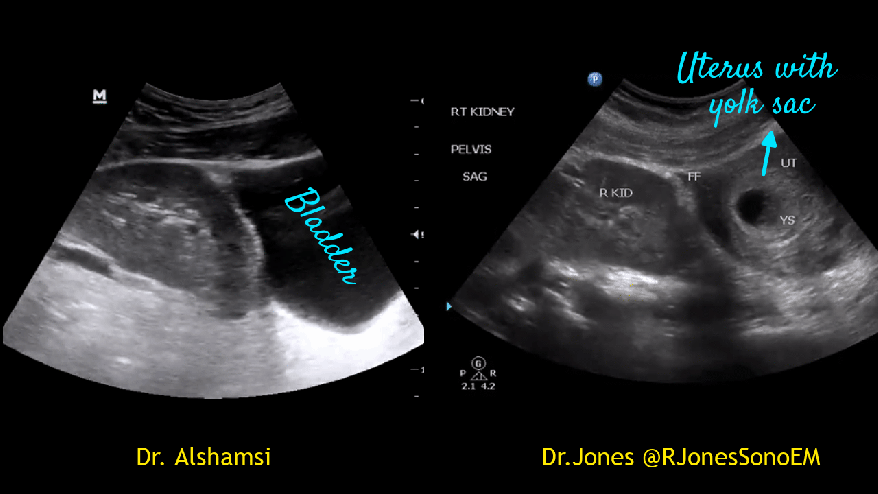

Here are two more examples. In females, a palpable pelvic kidney might be confused with a mass leading to unnecessary CT/MRI.